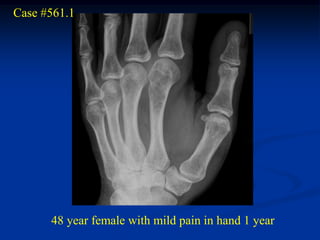

Case #561.1

48 year female with mild pain in hand 1 year

Cor T-1   STIR   Gad

Axial T-1         T-2 FS

Gad